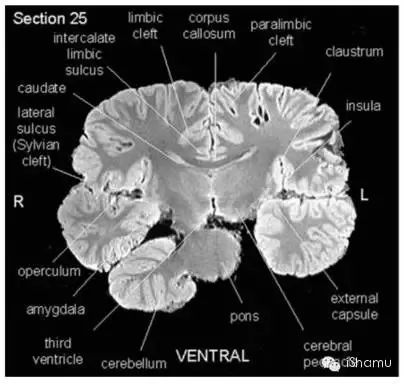

另外有一篇文献:“Neuroanatomy of the Killer Whale (Orcinus orca) From Magnetic Resonance Images”, 由神经生物学家Lori Marino et. al.于2004发表。该研究小组利用核磁共振成像技术,获得了宝贵的虎鲸脑部结构的图片。截了几张figure举几个栗子:

(Lori Marino et. al., 2004)

有医学背景的侠客朋友也应该看出来了。虎鲸的脑部解剖结构和人类脑部结构惊人的相似。同样有着高度折叠的大脑皮层沟回,有着形态和位置上高度相似的脑区(例如皮层,小脑,脑干,基底神经节),而且他们控制认知和情感的重要脑区Frontal lobe和Basal Ganglia也非常发达,同时也有着相对发达的参与记忆形成和学习的Limbic system包括著名的海马区,并且有着发达的Thalamus(丘脑)。